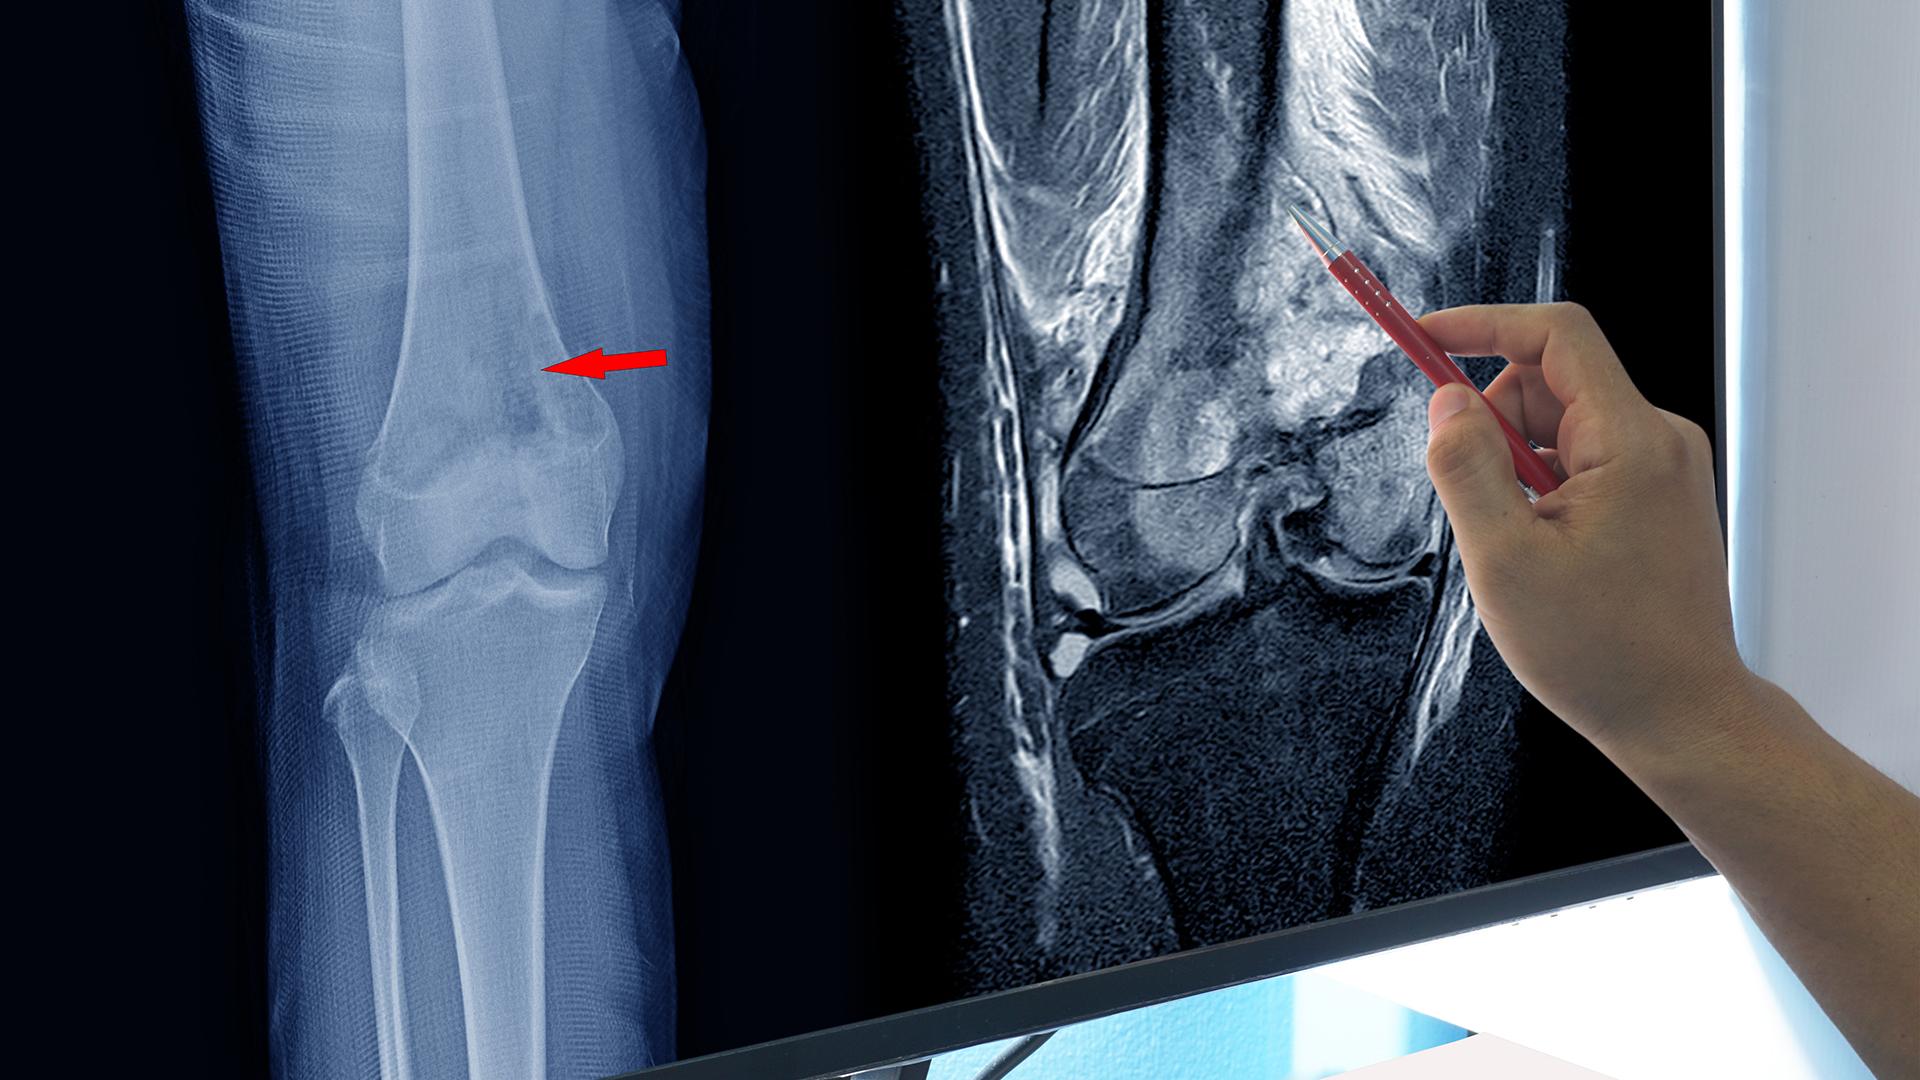

TheEwing Sarcoma Treatment Market is witnessing robust growth driven by advancements in targeted therapies and increasing incidence rates. Continuous innovation in treatment modalities and expanding market opportunities are creating a dynamic industry landscape. This blog presents an in-depth market analysis highlighting market size, current events, geopolitical impact, SWOT, and key players...